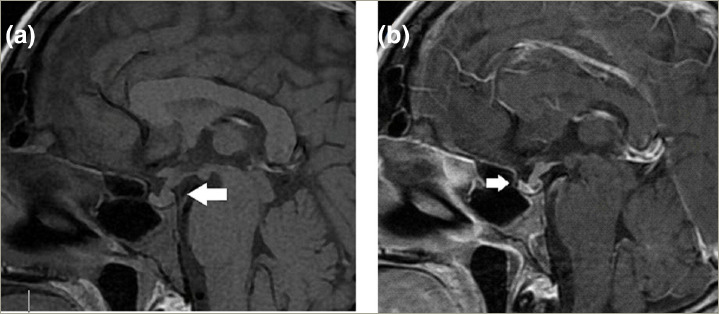

Pituitary infiltration by systemic lymphoma is an exceedingly rare occurrence. Given its high mortality rate, it is crucial to recognize its clinical, biochemical and radiological features in order to provide timely intervention. We present the case of a 26-year-old male with a history of human immunodeficiency virus (HIV) infection who presented to the hospital with severe anemia, persistent fever, weight loss and diarrhea over the previous 4 months. Physical examination revealed a compromised general condition, fever, pallor, hepatomegaly and lymphadenopathy. Cervical lymph node biopsy confirmed Burkitt lymphoma (BL). During hospitalization, the patient developed polyuria, polydipsia, hypernatremia, fluid-resistant hypotension and hypoglycaemia. Corticosteroid therapy was initiated due to suspected adrenal insufficiency, resulting in clinical improvement but exacerbation of polyuria and hypernatremia. Plasma and urinary osmolarity confirmed arginine vasopressin deficiency, and assessment of anterior pituitary reserve revealed hypopituitarism, necessitating hormonal replacement therapy. Sellar magnetic resonance imaging with contrast revealed pituitary infiltration. The patient subsequently developed septic shock and died. BL accounts for approximately 10% of the cases of pituitary infiltration associated with lymphoma. Clinical presentation is heterogeneous, with panhypopituitarism often serving as the initial manifestation. Sellar magnetic resonance imaging plays a pivotal role in the differential diagnosis. Management typically entails chemotherapy, immunotherapy, radiation and hormonal replacement therapy. This case report describes a patient with BL and HIV infection who developed panhypopituitarism due to pituitary infiltration, an exceedingly rare presentation considered a medical emergency.